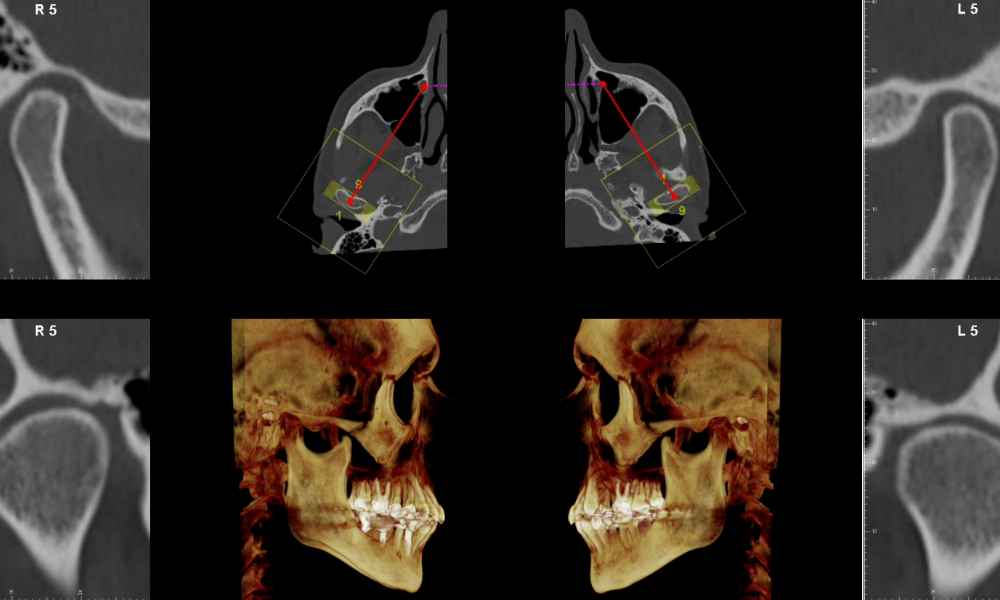

DIAGNÓSTICO 3D

Actualmente contamos la Tomografía Axial Computarizada (TAC) que nos ofrece muchísima más información y la posibilidad de reconstrucciones 3D